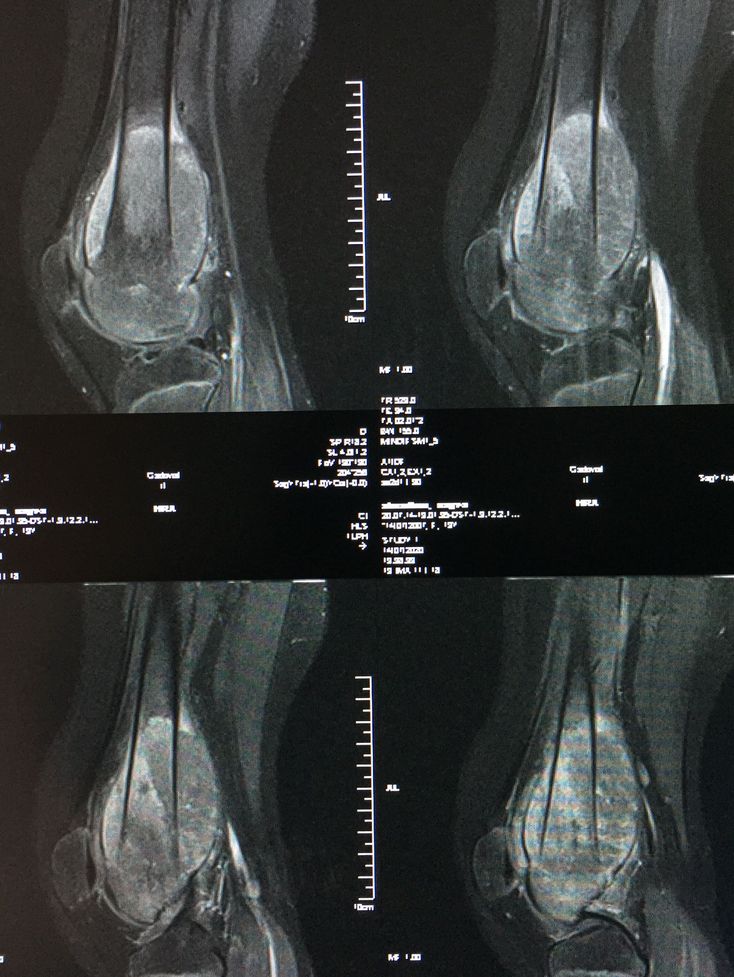

F 13y pain in rt knee this mri with contrast t1 fat sat sag

Diagnosis case ?

Posterior femur fibrosis